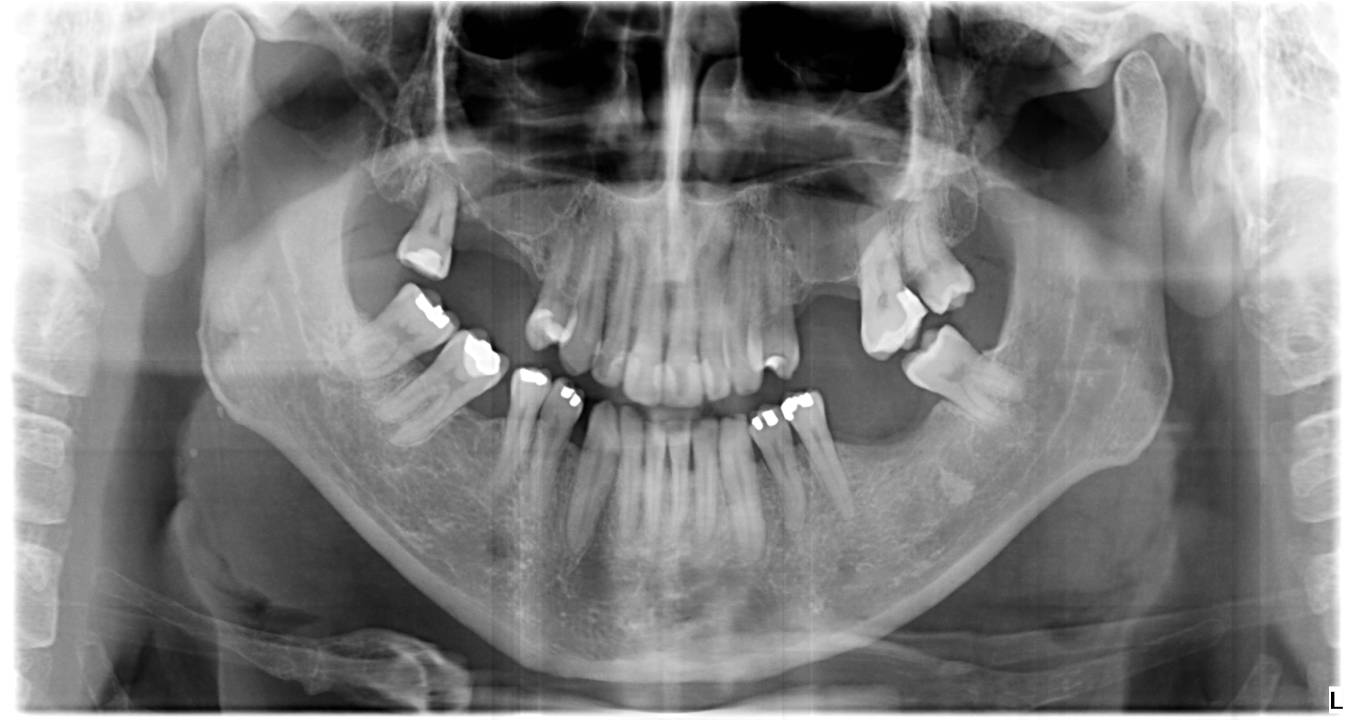

Regeneración ósea

En casos de pérdida de hueso, realizamos injertos óseos para recuperar el volumen necesario antes de colocar implantes dentales. De esta forma, garantizamos una base sólida y segura para restauraciones duraderas.